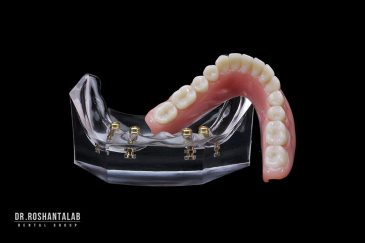

🔸کاشت ایمپلنت فلپ لس یا بدون جراحی و بدون بخیه زیر سه دقیقه

🔸 کاشت دندان یک روزه ( کشیدن و کاشت همزمان )

🔸 ایمپلنت دیجیتال و ساخت روکش دیجیتال